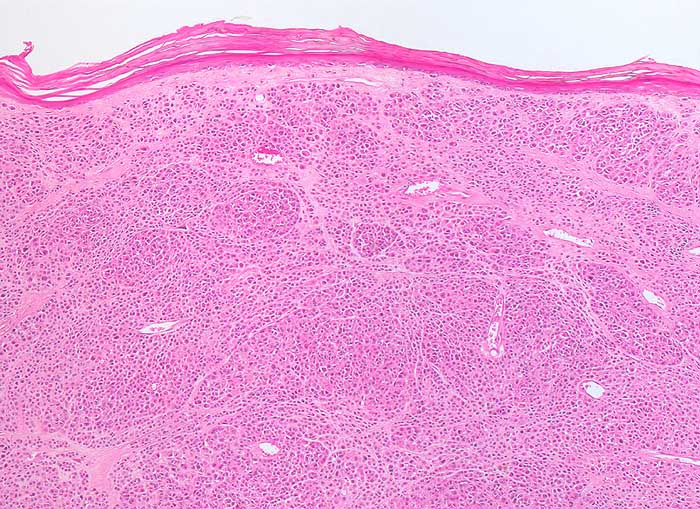

PathoPic – image database / PathoPic ID 6599 - noduläres malignes Melanom

noduläres malignes Melanom

Vertikale Wachstumsphase eines malignen Melanoms vom nodulären Typ. Atrophe hyperkeratotisch verhorndende Epidermis. Die Tumorzellen bilden solide Knoten. Die Epidermis wird nicht infiltriert.

Knotiger Tumor am Rücken

Histologie

50